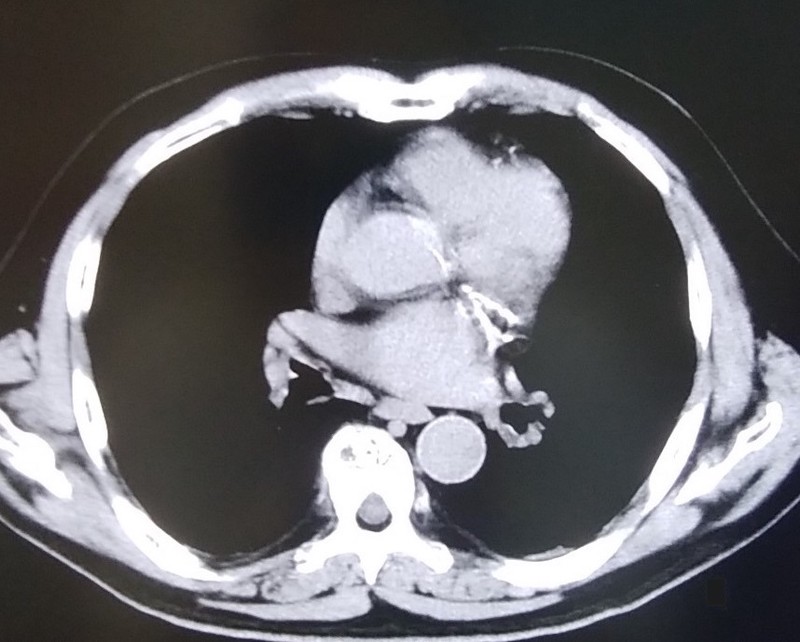

Bさんは、建設左官職で、アスベストはビル等で30年吸入しています。肺がんで死亡後、ご家族から相談がありました。わずかにCTで胸膜プラークを認めたので、名取が医師意見書を記載して遺族補償を労災保険に申請しました。数か月後に業務上として認定され、遺族補償をお受けになりました。

写真2 Bさん